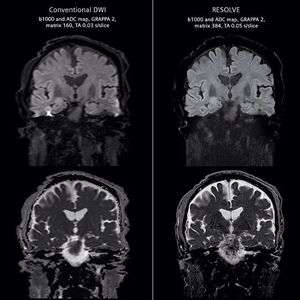

RESOLVE is a revolutionary new approach for obtaining high-quality, high-resolution DW images even in body regions strongly affected by susceptibility artifacts (figure). It reduces the distortions and delivers sharp imaging at higher spatial resolution.